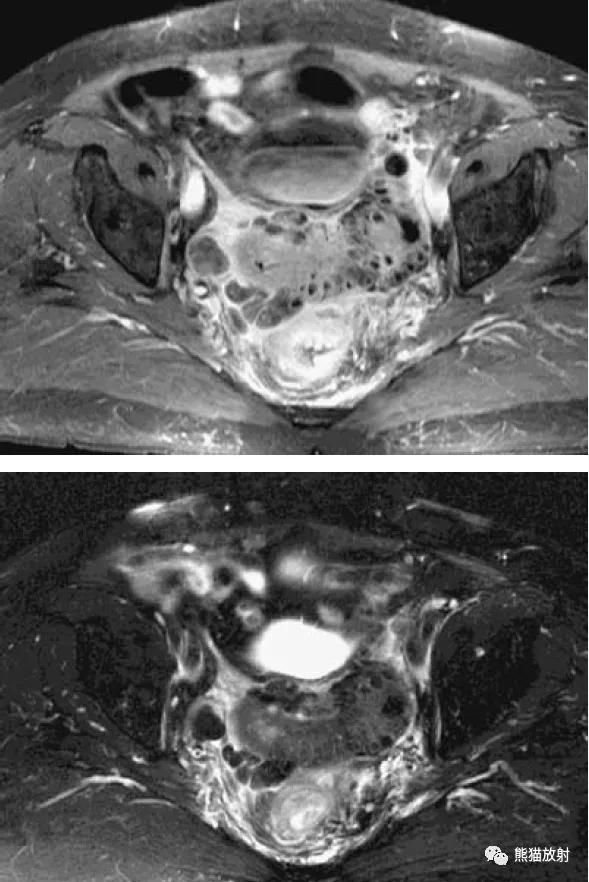

直肠周围脓肿(易误诊为直肠癌)。4个月前因增生行前列腺切除术,出现便秘。盆腔CT显示直肠病变并管腔变窄(箭头)。T1和T2加权图像显示直肠壁增厚和周围充满液体的结构(箭),提示脓肿或坏死性肿瘤。